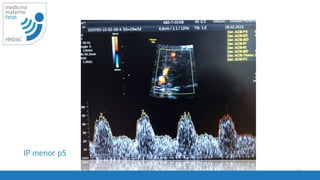

IP menor p5

57